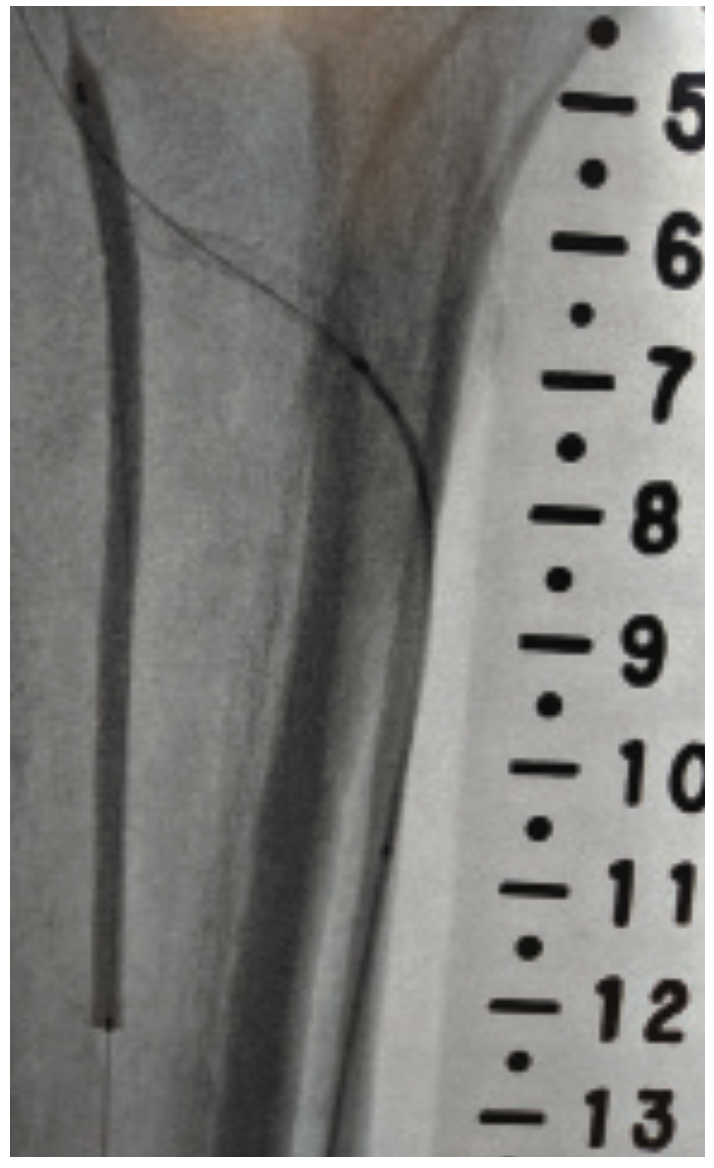

This is a 71-year-old male with a prior history of aortic valve replacement on coumadin, peripheral arterial disease, myocardial infarction, diabetes, and chronic kidney disease. He presented with a 3-month history of ischemic rest pain involving the left lower extremity, no wounds. He had previously undergone left superficial femoral artery (SFA) stenting for a chronic occlusion, but despite this, continued to have rest pain with peroneal-only runoff (Figures 1-4). He was brought in for left anterior tibial artery recanalization.

The patient qualified for the MicroMedical MicroStent trial, and both antegrade left lower extremity and retrograde dorsalis pedis access were obtained. The TASC II type D lesion of the anterior tibial artery origin was crossed with a V-18 wire (Boston Scientific), from below, and the wire was externalized via the antegrade sheath. Additionally, an .014-inch wire and balloon were placed into the tibioperoneal trunk and a 3 mm balloon was inflated across the origin of the anterior tibial artery. This “SOBE balloon protection technique” was used both to mark the origin of the anterior artery as well as serve as a buttress for placement of the stent (Figure 5). A 3 mm x 40 mm MicroStent was chosen and advanced through the 3 French (Fr) sheath from the dorsalis pedis access to the anterior tibial artery origin. The stent was placed across the lesion with precision to the origin. A 3 mm balloon was then inserted through the portal access and the stent was dilated to profile. Then the tibioperoneal trunk balloon was deflated and completion angiography was performed. Inline flow had now been created to the foot via the peroneal and anterior tibial arteries (Figure 6).